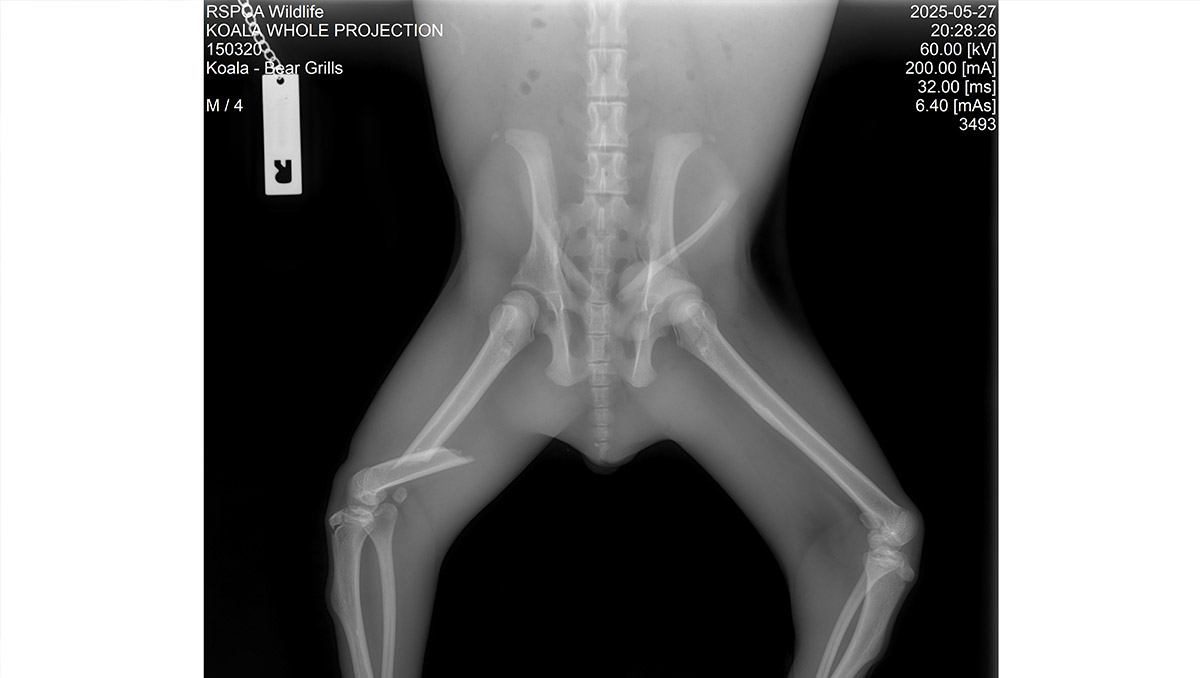

ABOVE: The X-ray showing Bear’s broken leg.

Image courtesy of RSPCA Queensland.

‘It’s great news that Bear is recovering well after his surgery to repair a fractured femur,’ she says.